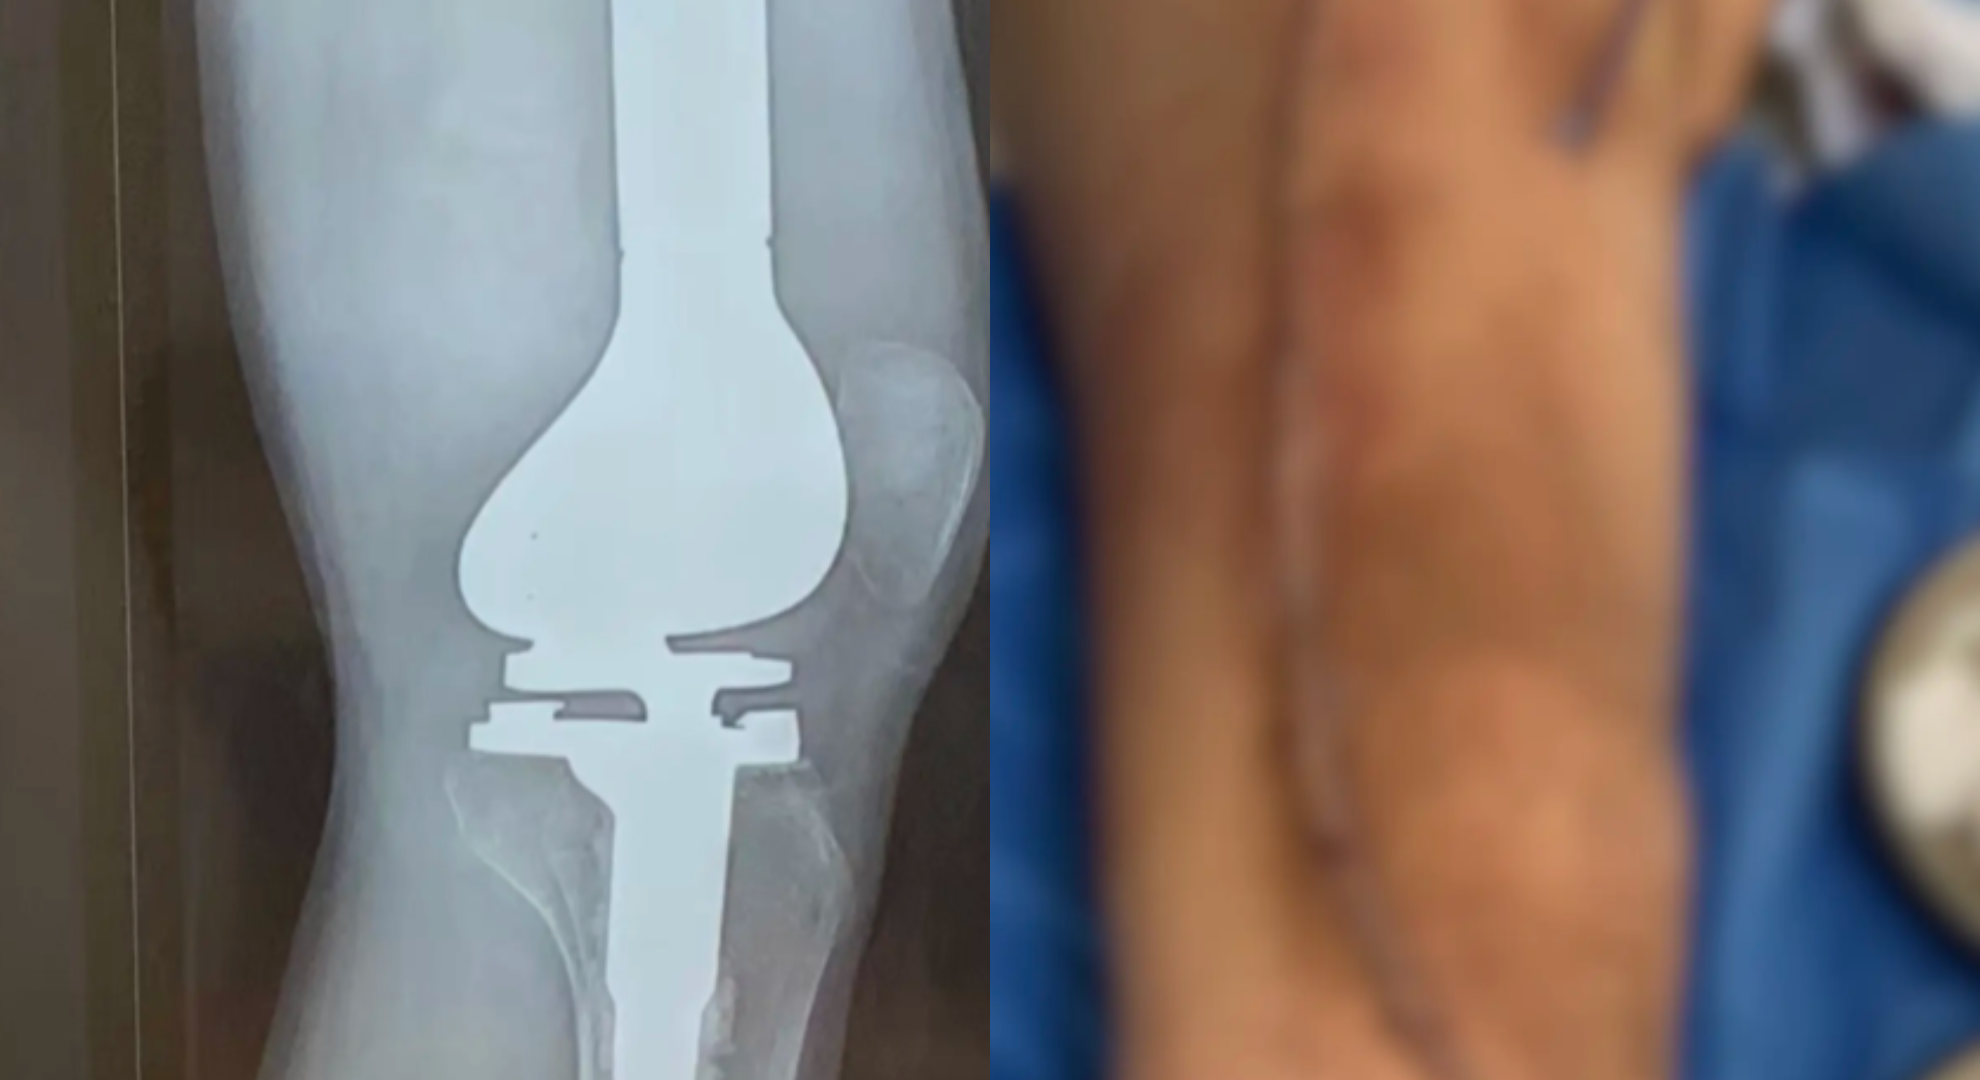

綜合《極目新聞》《新聞晨報》等陸媒報導,抗癌少年「晟寶」15歲升上高中後經常因為腿痛而輾轉難眠,起初家人還以為只是生長痛,帶他四處就醫並進行針灸治療,但都不見成效,後來眼見晟寶經常半夜痛醒,家長才意識到問題的嚴重性,帶人去醫院檢查後,確認他罹患骨肉瘤。在確診後,醫生曾建議截肢,但經過化療、手術後,晟寶勉強保住下肢,但腿上也留下了一道長達43公分、狀似蜈蚣的疤痕。

▲晟寶在接受治療後勉強保住下肢,但腿上也留下了一道長達43公分、狀似蜈蚣的疤痕。(圖/翻攝自抖音)